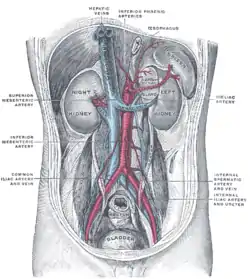

Animated Volume rendered CT scan of abdominal and pelvic blood vessels. Posterior abdominal wall, after removal of the peritoneum, showing kidneys, suprarenal capsules, and great vessels. (Hepatic veins labeled at center top.)

Posterior abdominal wall, after removal of the peritoneum, showing kidneys, suprarenal capsules, and great vessels. (Hepatic veins labeled at center top.) Human embryo with heart and anterior body-wall removed to show the sinus venosus and its tributaries.